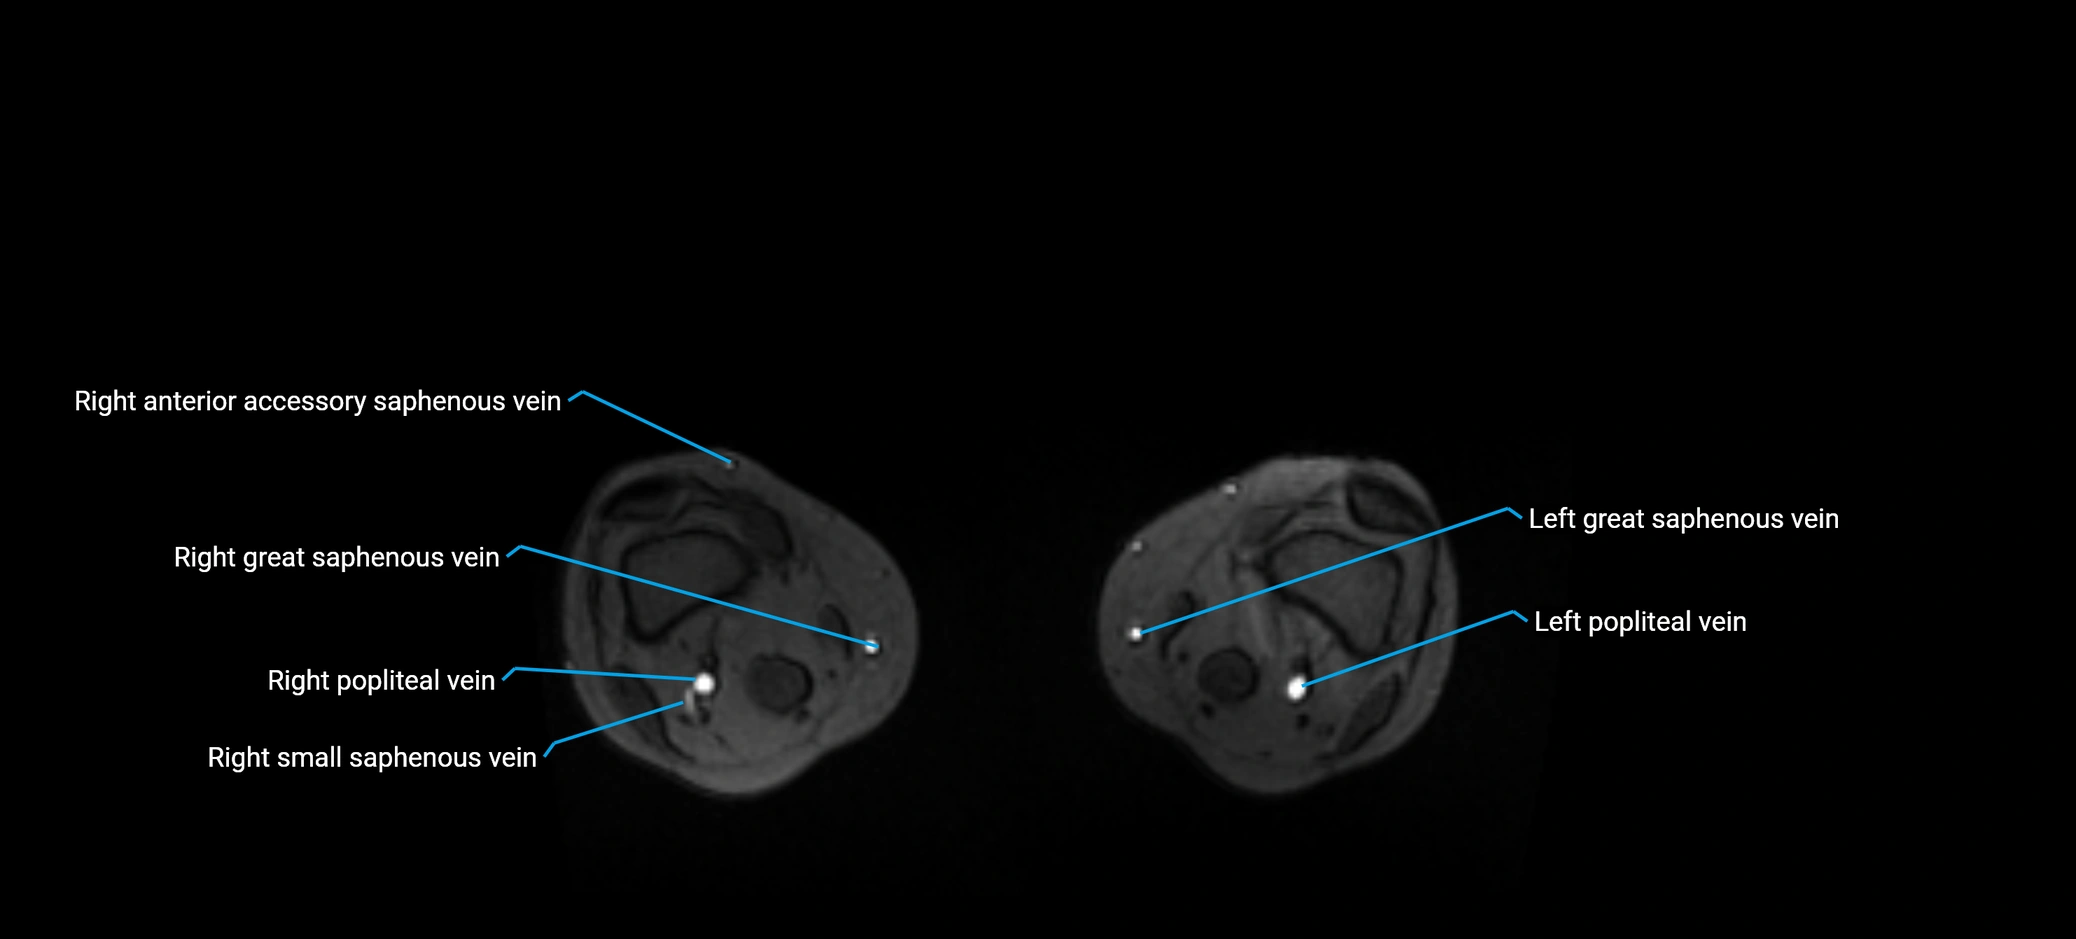

MRI image

image